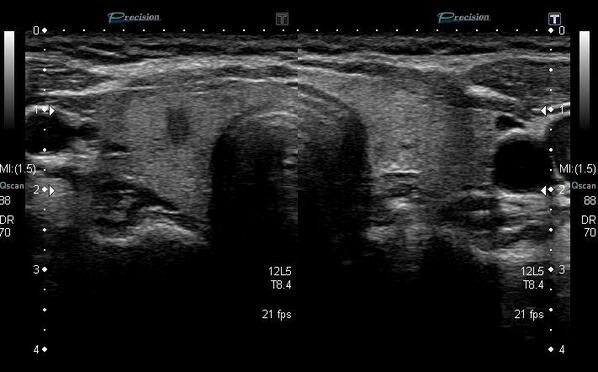

因みに、甲状腺癌(画面左)黒く抜けたところが、ガン。これでも大きさは5ミリ程度。時間があれば、この画像が流れたはず。 pic.twitter.com/1r3dGE8AVY